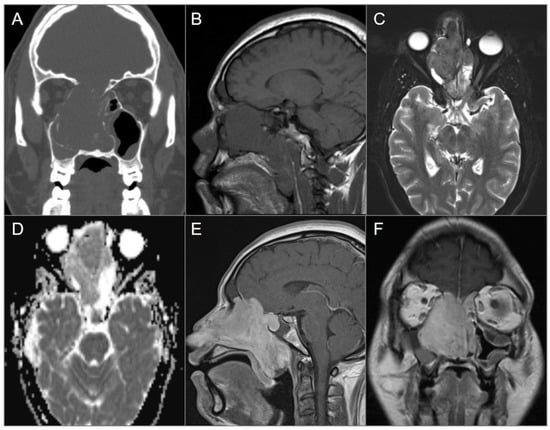

4.3.3. Langerhans Cell Histiocytosis

4.3.4. Cholesterol Granuloma